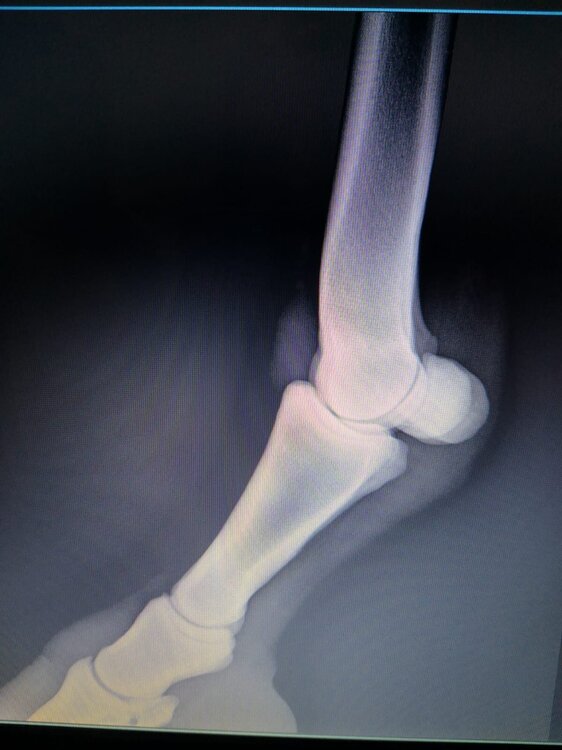

Salve volevo chiedervi qualche informazione in merce tò a un problema che ho avuto con la mia puledra. Qualche settimana fa mentre stavo lavorando alla corda è scivolata urtato l'arto posteriore sinistro. Arrivati in box ho messo dell'acqua a pressione perché si era gonfiato sia il nodello sia il pastorale. Già l'indomani l'arto era sgonfio ritornato normale, quindi ho continuato a lavorarla. Ma dopo qualche giorno di lavoro alla corda leggerissimo, al rientro in box ho notato che sia il nodello che il posturale gonfiavano nuovamente. Allora ho chiamato il veterinario che ha detto che la cavalla aveva una lussazione e mi ha insegnato come cura una fasciatura con della creta per 24h per cinque giorni e un antinfiammatorio. Dopo un paio di giorni la fasciatura ha fatto come delle vesciche e il gonfiore è aumentato dal pastorale alla garra. Abbiamo chiamato un altro veterinario abbiamo fatto vedere anche a lui la cavalla e diceva che poteva essere la frattura del ditino, ma si dovevano fare le lastre per essere sicuri. Ora abbiamo fatto le lastre e il radiologo dice che c'è dell'infiammazione ma non c'è niente di grave. Il veterinario,viste le lastre dice che deve essere operata. Allora abbiamo consultato un'altro veterinario che dice che la cavalla non ha assolutamente niente. Ora io vi allego le radiografie, datemi un vostro parere perché non só più cosa fare. Grazie